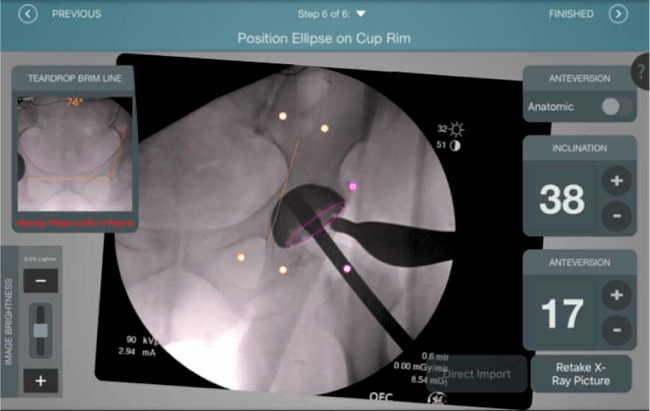

Mayor nivel de información intraoperatoria facilita la colocación correcta de los implantes:

• Inclinación y anteversión de la copa acetabular para una correcta colocación del implante.

• Verificación de la posición deseada del implante que potencialmente puede ayudar a reducir la probabilidad de dislocación protésica y aumentar la estabilidad de la articulación.